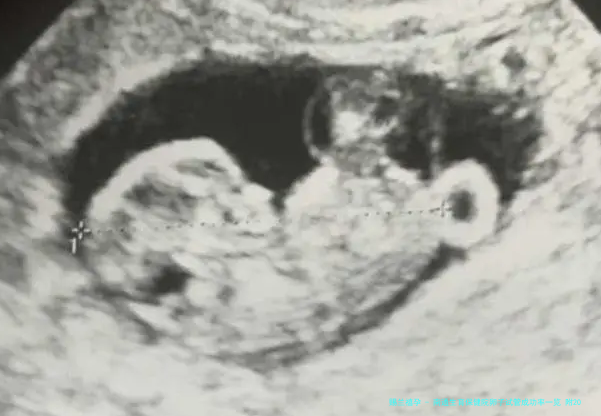

试管技术,即借助第三方卵子与试管婴儿技术融合,帮助因各式各样原因无法自然怀孕的夫妻实现生育梦想。南通生育保健院在这方面范围累积了丰富的经验,拥有一支专业的医疗团队和专业的实验室配备,保障每一个步调都谨严而精准。

试管技术的成功率受多种要点影响,包括女性年纪、卵子质量、子宫内环境以及医疗团队的专业水平等。南通生育保健院在这方面的成功率稳固在60%左右,这一数字既展现了医院的专业水平,也给予了病人极大的信心。自然每位患者的详细情况不同,实际成功率还需结合个人状况评介。